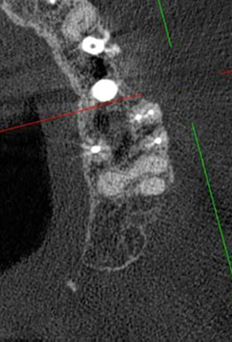

Перелечивание зуба с кистой под микроскопом

Проблема: У пациента отек щеки, боли самопроизвольные, усиливающиеся при приеме пищи, неудачное первичное лечение зуба (старыми методами).

Цель лечения: Помочь пациенту избавиться от болевых ощущений, избежать удаления зуба.

Лечение: Проведено эндодонтическое перелечивание зуба под дентальным микроскопом, что позволило точно выявить анатомические особенности корневых каналов и устранить последствия ранее некачественного лечения. После купирования воспалительного процесса (киста) каналы герметично запломбированы. Коронковая часть зуба восстановлена для сохранения функции и герметичности до этапа постоянного протезирования.

Результат: После проведённого лечения болевые ощущения полностью устранены, отёк щеки исчез, воспалительный процесс купирован. Зуб сохранён, восстановлена его функция. Установлена коронка, что позволило полностью восстановить анатомическую форму и жевательную эффективность зуба.